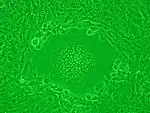

Syncytia can also form when cells are infected with certain types of viruses, notably HSV-1, HIV, MeV, SARS-CoV-2, and pneumoviruses, e.g. respiratory syncytial virus (RSV). These syncytial formations create distinctive cytopathic effects when seen in permissive cells. Because many cells fuse together, syncytia are also known as multinucleated cells, giant cells, or polykaryocytes.[12] During infection, viral fusion proteins used by the virus to enter the cell are transported to the cell surface, where they can cause the host cell membrane to fuse with neighboring cells.